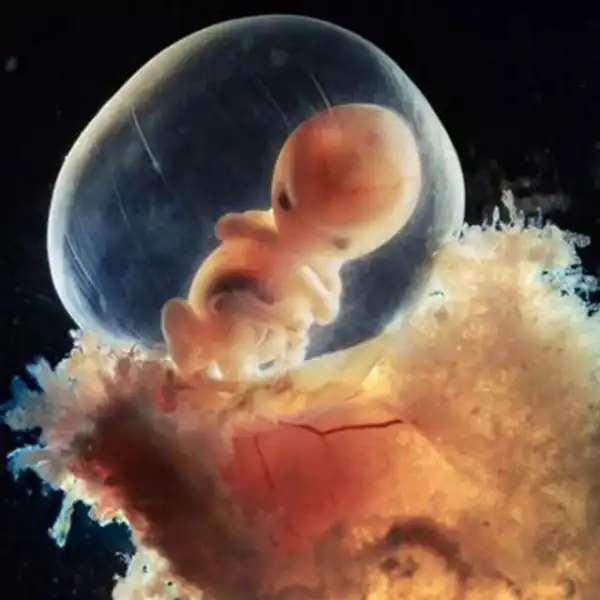

28-й день после оплодотворения..

4 с половиной недели...

Пятинедельный эмбрион, длина 9 мм, уже угадывается лицо с отверстиями для рта, ноздрей и глаз.

40 дней. Наружные клетки зародыша срослись с рыхлой поверхностью матки и образуют плаценту, или детское место. Это губчатый кусок плоти служит человеку в первые девять месяцев его жизни и легкими, и желудком, и печенью, и почкой...